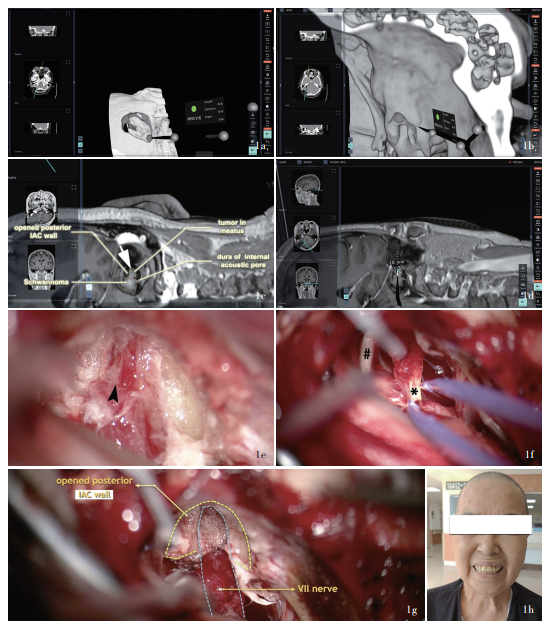

Background: Neurosurgery developed rapidly with technology advancing. Concept of digit-intelligent neurosurgery becomes mature and augmented reality (AR) technology shows great potential in future neurosurgical operations. The feasibility and applicability of AR assisted technology is currently the most important topic in clinical research. Methods: Four cases engaged from January to December 2024 in Department of Neurosurgery of Beijing Tsinghua Changgung Hospital with vestibular schwannoma (one case), intracranial aneurysm (2 cases) and subclavian artery (SA) occlusion caused vertebral artery steal syndrome (one case) have been conducted tumor resection, internal carotid artery (ICA)-posterior communicating artery (PCoA) aneurysm clipping and common carotid artery (CCA)-SA bypass, respectively. Using presurgical imaging data-based Surgical AR reconstruction on the HoloLens 2 platform, preoperative planning, surgical simulation, and intraoperative display were conducted. These were then compared with surgical practices and postoperative imaging data to qualitatively evaluate their effectiveness in assisting neurosurgery. Results: 1) Vestibular schwannoma resection: compared to the preoperative AR assisted simulation, we fully replicated the procedures of retrosigmoid approach craniotomy, removal of the posterior wall of internal auditory canal, and the exposure and removal of the internal auditory canal tumor during surgical practice. Facial nerve function was preserved intact during the surgery and reached House-Brackmann grade Ⅰ, but effective hearing was not preserved. Postoperative imaging data showed non-significant difference compared to preoperative simulation and surgical practice. The modified Rankin Scale (mRS) assessed postoperatively was 2. 2) ICA-PCoA aneurysm clipping: compared to the presurgical AR assistance, we fully replicate the procedures of lateral supraorbital craniotomy, removal of anterior clinoid process and the exposure and clipping of the neck of aneurysm. Postoperative imaging data showed non-significant difference compared to preoperative simulation. Postoperatively symptoms such as eye pain, ptosis, and double visian were completely relieved and the mRS was 0 after 6 months. 3) Basilar artery apex aneurysm clipping: based on preoperative simulation, we opted for the orbito-zygomatic approach during surgery to provide full exposure of the aneurysm neck and direct visualization of the bilateral P1 segment of posterior cerebral artery (PCA), offering better safety compared to the subtemporal approach. In surgical practice, lateral sulcus was separated, basilar artery and aneurysm was exposed and clipped via carotid spaces. Postoperatively occlomoter nerve was well recovered mRS was 0 after 6 months. 4) CCA- SA bypass: critical muscles and vessels on the neck were located intraoperatively on the body surface with AR assistance. CCA and SA were fully exposed and artificial vessel was anastomosed. Postoperative CTA 3D reconstruction suggested the blood flow was patent. The dizziness did not recur, and the blood pressure in the upper limb on the affected side returned to normal. Postoperative mRS was 0 after 6 months. Conclusions: The application of AR technology in neurosurgical procedures allows for preoperative planning, surgical simulation, and intraoperative display. It aids young surgeons in quickly understanding complex anatomical structures and shortens the learning curve, holding significant clinical value and promising application prospects.

研究背景: 计算机技术和人工智能技术的发展使数智神经外科学日趋成熟, 增强现实技术作为新兴技术已在神经外科手术中展现出巨大潜力, 探讨该项技术辅助神经外科手术的可行性和实用性将是现阶段临床研究的重要议题。方法: 纳入4例2024年1-12月在清华大学附属北京清华长庚医院行神经外科手术的前庭神经鞘瘤(1例)、颅内动脉瘤(2例)和锁骨下动脉闭塞致椎动脉盗血综合征(1例)患者, 分别接受前庭神经鞘瘤切除术、颈内动脉-后交通动脉动脉瘤夹闭术和颈总动脉(CCA)-锁骨下动脉(SA)搭桥术; 将术前常规影像学数据导入Surgical AR软件, 基于HoloLens 2平台进行术前规划、模拟手术和术中实时显示, 并与实际手术操作和术后影像学数据对比, 定性分析增强现实技术辅助神经外科手术的疗效。结果: (1)前庭神经鞘瘤切除术: 与术前增强现实技术模拟手术(模拟手术)对比, 实际手术完全复现经枕下乙状窦后入路开颅、内耳道后壁磨除、内耳道内肿瘤显露和切除的操作过程, 术中面神经保护完好, 术后面神经功能达House-Brackmann分级Ⅰ级, 但未保留有效听力; 术后1周三维重建CT与术前模拟和术中实际所见无明显差异; 术后6个月改良Rankin量表(mRS)评分为2分。(2)颈内动脉-后交通动脉动脉瘤夹闭术: 与术前模拟手术对比, 实际手术完全复现经眶上外侧入路开颅、磨除前床突、显露动脉瘤颈并夹闭的手术过程; 术后三维重建CTA与术前模拟无明显差异; 术后6个月, 眼部胀痛、上睑下垂、复视等症状完全缓解, mRS评分为零。(3)基底动脉尖动脉瘤夹闭术: 根据术前模拟结果, 经眶颧入路对动脉瘤颈的显露更充分且术者可于直视下完全夹闭动脉瘤并保护双侧大脑后动脉P1段, 操作安全性明显优于经颞下入路; 实际手术中选择经眶颧入路, 分离外侧裂经颈内动脉-动眼神经间隙显露基底动脉和动脉瘤、夹闭动脉瘤; 术后6个月mRS评分为零, 动眼神经功能恢复良好。(4)CCA-SA搭桥术: 术中通过增强现实技术辅助颈部重要肌肉、血管体表定位, 充分显露颈总动脉和锁骨下动脉, 人工血管吻合; 术后三维重建CTA显示桥血管通畅; 患者头晕症状未再发作, 患侧上肢血压恢复正常; 术后6个月mRS评分为零。结论: 增强现实技术用于神经外科手术可术前手术规划、手术模拟和术中引导, 有助于青年医师快速理解复杂的解剖结构、缩短学习曲线, 具有重要的临床价值和广阔的应用前景。